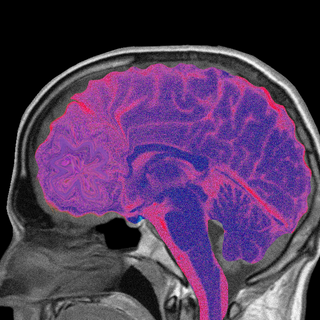

Blood types are determined by the presence or absence of antigens on the surface of red blood cells. If transfused blood does not match that of the receiver, it could trigger alloimmunization – the generation of antibodies against a blood group antigen. This poses several complications. For instance, during pregnancy where the mother’s and fetus’s blood mixes through the placenta, it could cause an immune reaction that could result in the breakdown of red blood cells in the fetus or even the death of the unborn child.